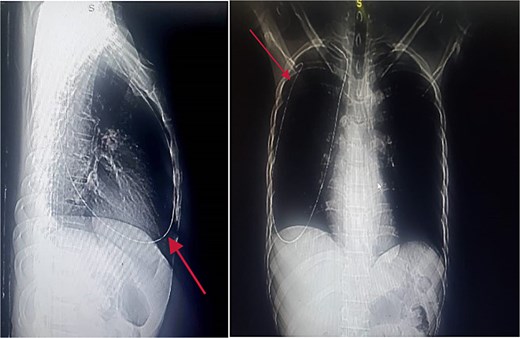

An immediate chest X-ray revealed the metallic guide wire within the right hemithorax, coursing from the anterior medial aspect of the cupola to the posterolateral aspect of the second intercostal space, with a notable curve at the diaphragm (Fig. 2).

Chest X-ray posterior anterior and lateral view showing the intrathoracic metallic guide. The wire’s thin, linear shape is clearly visible, with an abrupt change in course around the cupola indicating its unintended migration from the subclavian vein into the chest cavity.